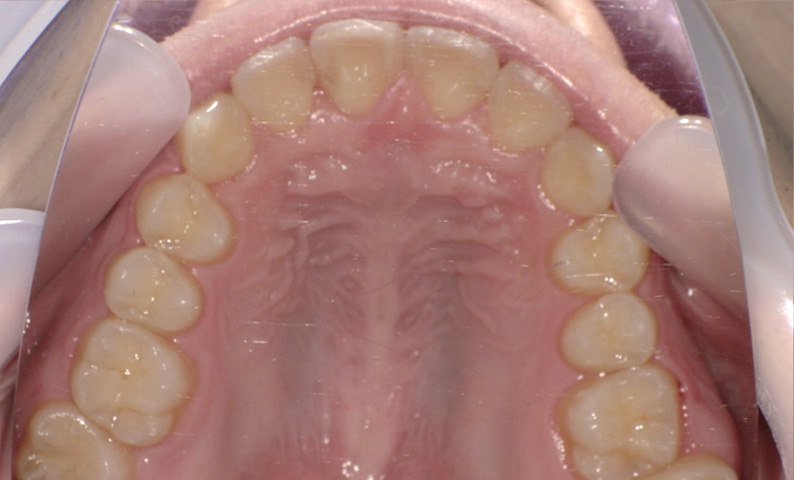

症例_009 「上下の前歯」症例

治療期間:7ヶ月金額:54万円+税20代女性捻転歯一部の反対咬合前歯のガタガタ

Before | After |

---|---|